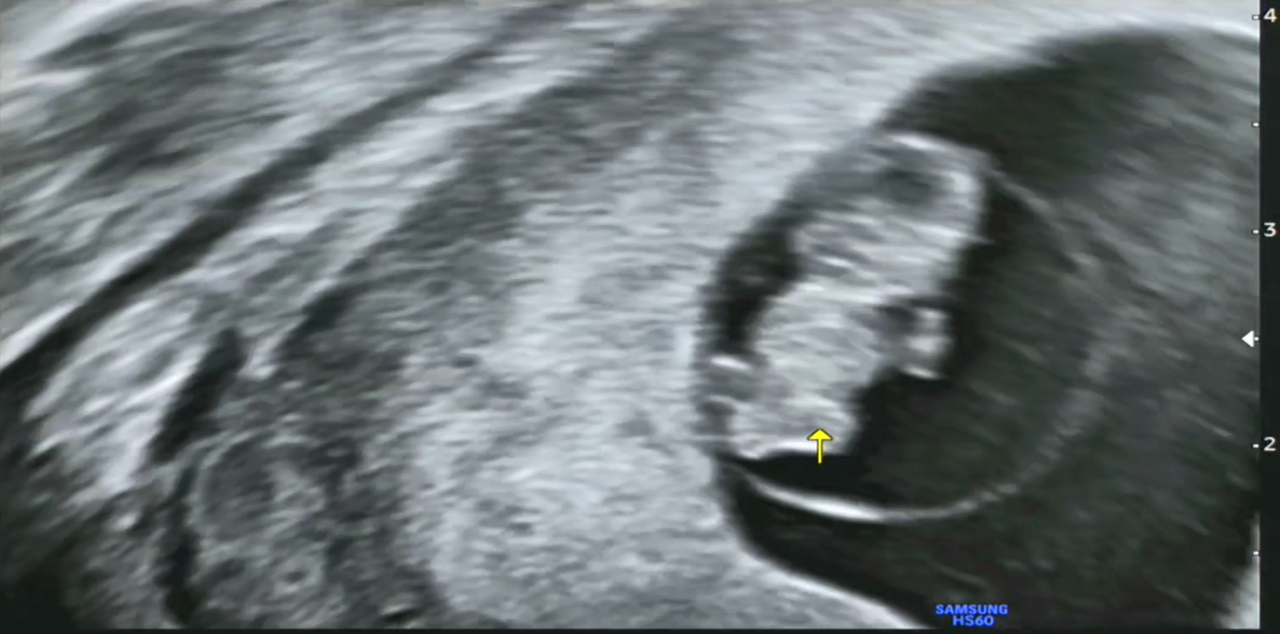

그리고 이때쯤 되면 머리와 몸의 크기가 같은 2등신이 되고 손발이 구별된다고 해서, 영상을 한번 캡처해 보았습니다. 제가 딸보고 머리가 크다고 했더니 '하리○ 젤리곰' 같다고 하네요. 언듯 보면 '겨울왕국의 올라프' 같이 보이기도 합니다. 태명이 '울라프'도 괜찮아 보이네요.

7주0일 다리.png

7주0일 심장.png

[왼쪽-다리, 오른쪽-심장]